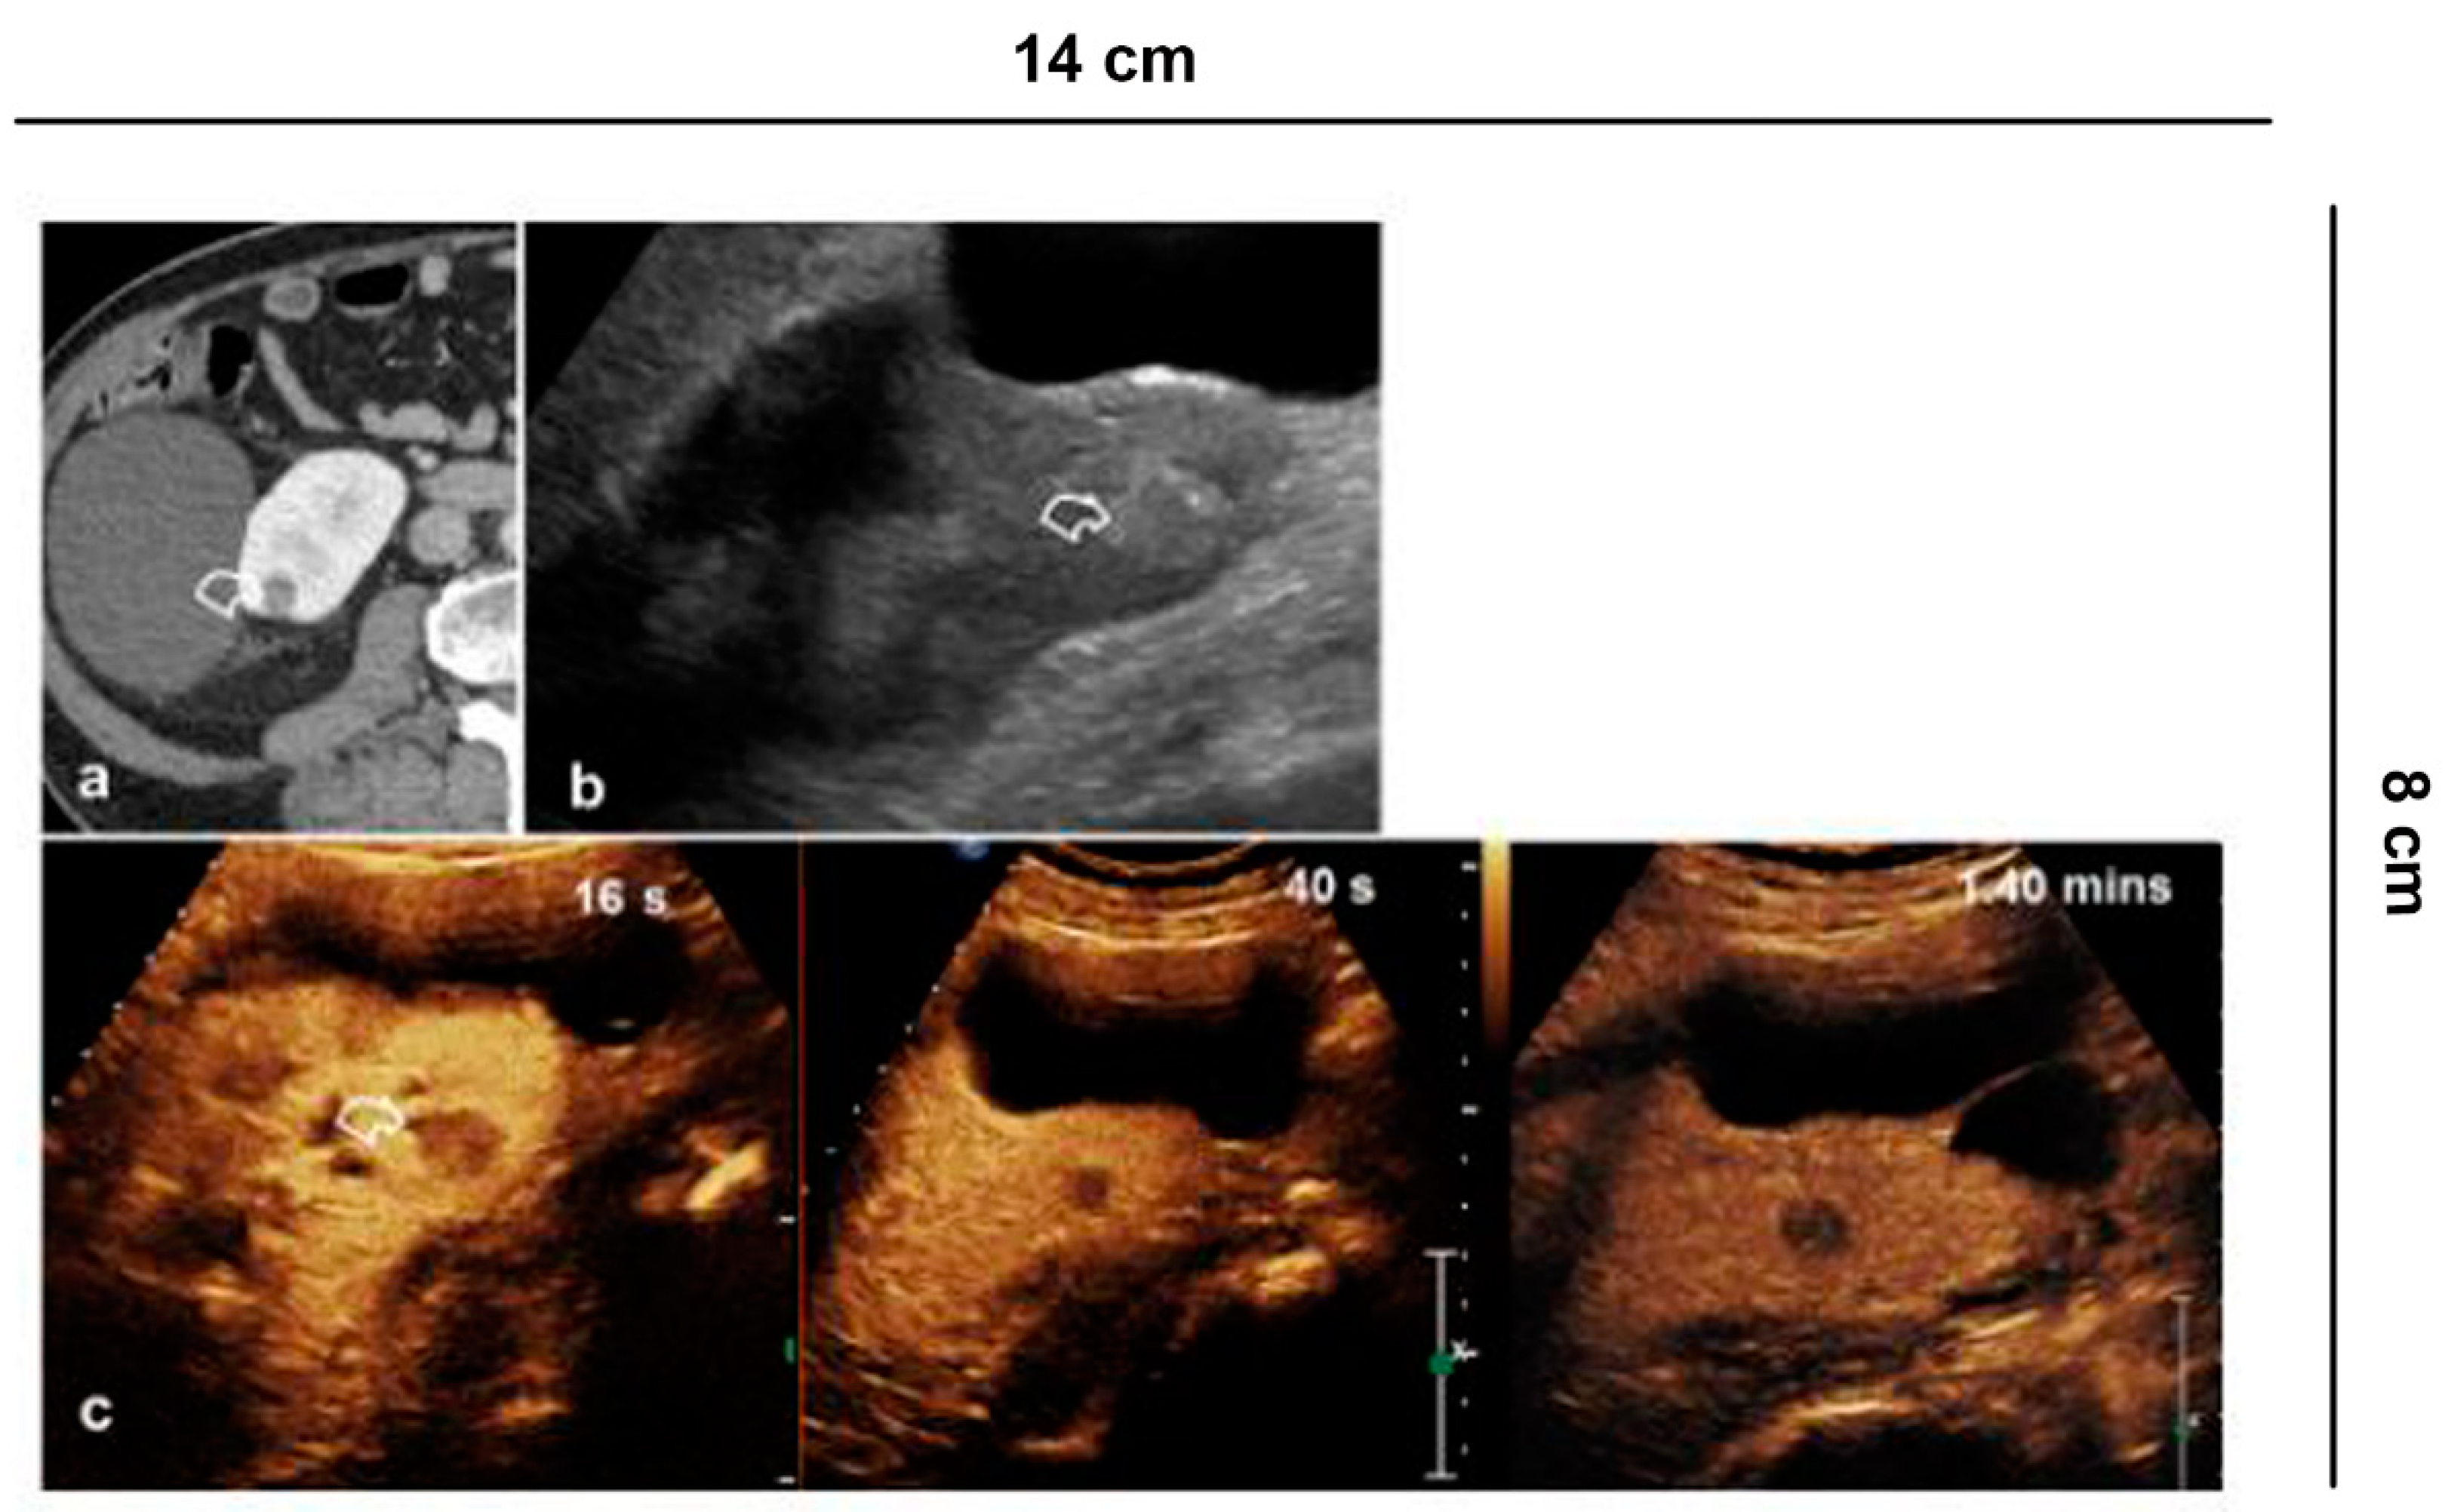

CT remains the gold standard for the study of kidney trauma due to its panoramic view and its greater sensitivity compared to ultrasound. Thanks to its exclusively vascular nature, CEUS increases the sensitivity of US for the detection of traumatic lesions [] allowing the study of all the vascular phases (arterial, venous and parenchymal) in real time, but above all it is useful in the follow-up in cases of conservative therapy (Figure 9) [].

Figure 9.

Vascular lesions. 35-year-old male patient with abdominal trauma treated conservatively. (a) CT without contrast medium shows parenchymal hyper-density from recent hematoma (arrowhead) at the lower pole of the left kidney; (b) A pseudoaneurysm (curved arrow) is recognized in the arterial phase, while in the (c) nephrographic phase the parenchymal contusion is more clearly recognized and the pseudoaneurysm is less visible; (d) B-mode US shows inhomogeneous echogenic areas (asterisks) corresponding to the contusions; (e) CEUS adequately shows all the vascular phases of the pseudoaneurysm (curved arrow) and the perirenal hematoma (asterisk); (f) Follow-up performed on 7th day.

In addition, active bleeding can be recognized with some extravasated contrast medium bubbles and pseudoaneurysms can be detected. It should be remembered that the excretory system cannot be studied with CEUS and therefore when damage to the excretory tract is suspected, CT is mandatory.